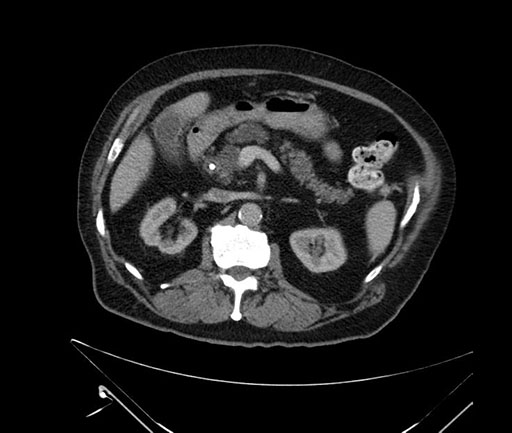

Axial - 3 months prior

Axial - stented